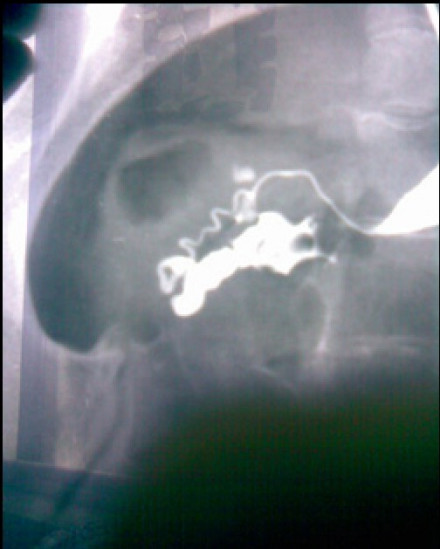

(5)输卵管造影:输卵管造影是目前检查输卵管是否通畅的最好方法,造影检查是在电脑全程控制下,观察造影剂充盈宫颈、子宫及双侧输卵管时的形态,同时,摄片留下记录,能了解输卵管是否通畅,输卵管阻塞部位,同时可以了解子宫及输卵管形态,在临床应用上,仍有不可取代的作用。

输卵管管腔的诊断主要通过经X线的子宫输卵管造影检查,近端输卵管粘连主要表现为管腔的狭窄,管壁的毛糙。输卵管远端的粘连主要表现为壶腹部或者伞端的增粗扩张,远端的迂曲,延迟片有输卵管残留影等。